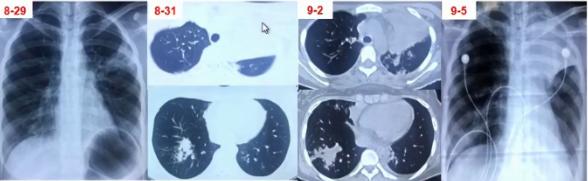

病例1

女性,15岁,既往曾行脊柱侧弯矫形术。因发热、咳嗽、咳黄痰1周入院。

发病后2天起予头孢曲松+阿奇霉素治疗至入院当日,日最高体温从39.9℃降至38.3℃,但发热、咳嗽、咳黄痰无进一步好转。

血常规检测:

• 发热第3天:WBC 5.34×109/L,N 0.659,CRP 1.063mg/dl

• 发热第7天:WBC 4.07×109/L,N 0.691,CRP 1.547mg/dl

CK 357.5 U/L,LDH 277.1 U/L

图1 患者的影像学以实变为主